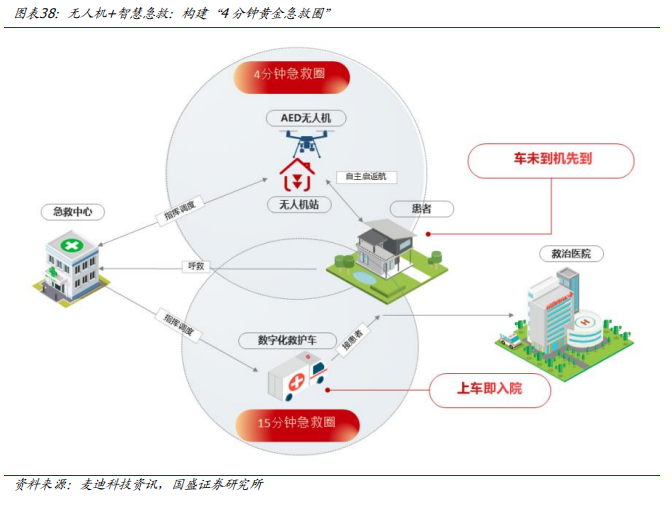

低空:低空经济与急救深度融合,实现AED无人机全国首飞。1)2024年以来全国已有27个省(市、自治区)在各地政府工作报告中提及低空经济,预计到2026年低空经济市场规模有望突破万亿元,2021-2026年CAGR约29.6%。2)医疗急救是低空经济落地的重要领域。2023年苏州市平均每天心搏骤停人数已增至10人以上,对心脏骤停患者在1分钟内实施心肺复苏,3至5分钟内进行AED除颤,可使患者存活率达到50%至70%,一旦超过黄金4分钟会造成不可挽回的后果,AED无人机的问世有利于解决了4分钟内AED到达的难题。3)麦迪科技无人机方案与智慧急救方案深度融合,通过对接120急救系统、医院临床信息系统,自动实现AED无人机的智能调度,2024年6月在全国首飞航空医疗救援系列MD127-I型AED无人机。4)目前,AED无人机需求具备较强确定性,AED倍增工程被纳入了苏州年度民生实事项目,明确要在全市公共场所已投放近1000台AED的基础上,再新增2000台以上;同时完成使用技能持证培训不少于1.3万人,同步开展市民持证培训1.5万人,合计培训2.8万人。

4.2构建AED无人机黄金急救圈,下游需求确定性强

心脏骤停人数激增,黄金4分钟至关重要。《中国心脏骤停与心肺复苏报告(2022年版)》显示,我国心脏骤停总体发病率97.1/10万。在我国,超过80%的心脏骤停以及猝死情况发生在医院外。而据苏州市急救中心发布的《2022年苏州市区院前急救数据报告》显示:2022年,苏州市区发生心搏骤停3400余人次,比2021年增加41%,平均每天约有9至10人心搏骤停;而到了2023年,平均每天心搏骤停的人数已增至10人以上。而“黄金4分钟”,则是对心脏骤停患者最佳的抢救时间窗口:统计结果显示,对心脏骤停患者在1分钟内实施心肺复苏,3至5分钟内进行AED除颤,可使心脏骤停患者存活率达到50%至70%。一旦超过“黄金4分钟”,往往造成不可挽回的后果。

AED无人机的问世,有望解决4分钟内AED到达的难题。该模式能够成功化解传统心脏骤停救援问题的两大障碍:

l一是原来都是由120接警后通知附近的志愿者到相应的地点去取AED,然后再赶赴现场救援,耗时又费力;现在一接警,志愿者、携带AED的无人机和救护车便一齐出动,形成了一个高效而完整的救援闭环。

l二是解决了AED的布点问题。无人机的起飞点就是急救体系的中转枢纽,枢纽常态化配备了相应的AED设备。这样可充分发挥无人机不堵车、高航速和自主精确导航的优势,快速到达更广阔的周边地域,一定程度上也大大降低了AED的布设成本。

全国首飞航空医疗救援系列MD127-I型AED无人机,麦迪科技低空经济创新中心成立。2024年6月18日,苏州瞄准心脏骤停这个“致命杀手”,在全国首飞航空医疗救援系列MD127-I型AED无人机,并率先发布基于全自主智能化AED无人机救援的低空救援整体解决方案。今后一旦正式投用,周边目击者只要第一时间拨打120,就能为发生心脏骤停的患者最快时间“呼”来AED(自动体外除颤器)这一“救命神器”,为挽救生命增添极大可能。首飞仪式上,麦迪科技股份有限公司与西北工业大学太仓智汇港管委会、西北工业大学航天学院空天动力技术创新团队三方共建,成立了麦迪科技低空经济创新中心。这个创新中心,瞄准的正是“低空+医疗”领域的技术创新与应用突破。

AED倍增工程被纳入了年度民生实事项目,AED无人机下游需求具备确定性。AED倍增工程被纳入了苏州年度民生实事项目,明确要在目前全市公共场所已投放近1000台AED的基础上,再新增2000台以上;同时完成使用技能持证培训不少于1.3万人,同步开展市民持证培训1.5万人,合计培训2.8万人。